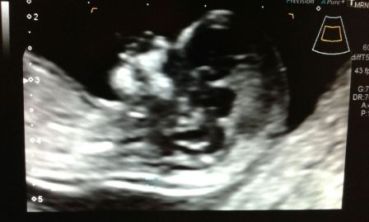

Translucencia nucal: ¿De qué se trata?